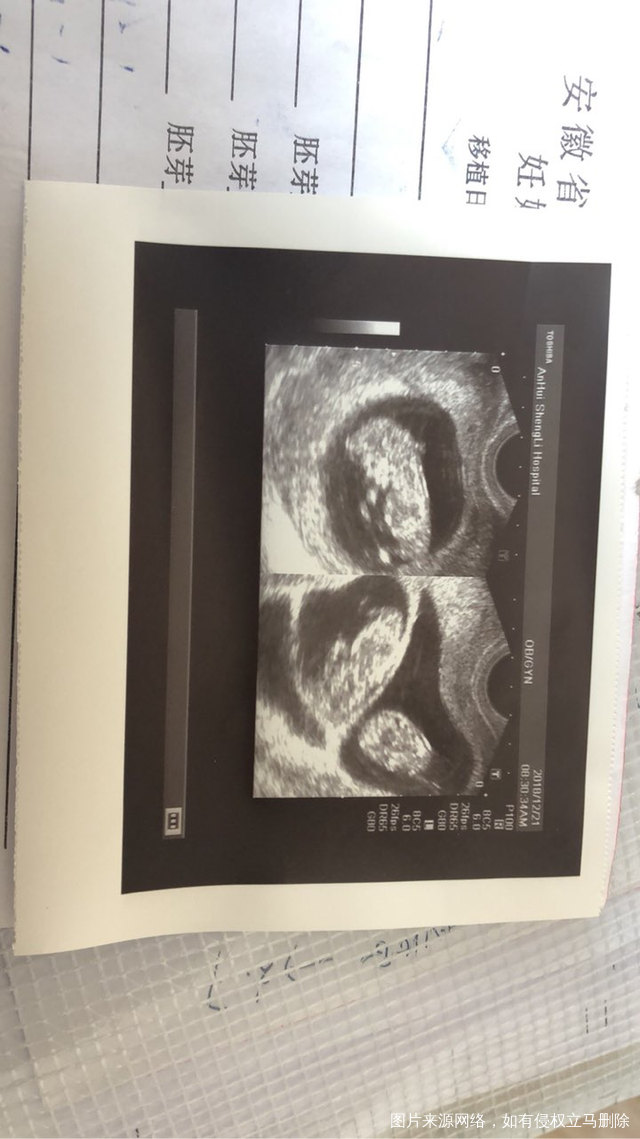

二超顺利通过,希望大家都能好孕

2018-12-22 10:57:41